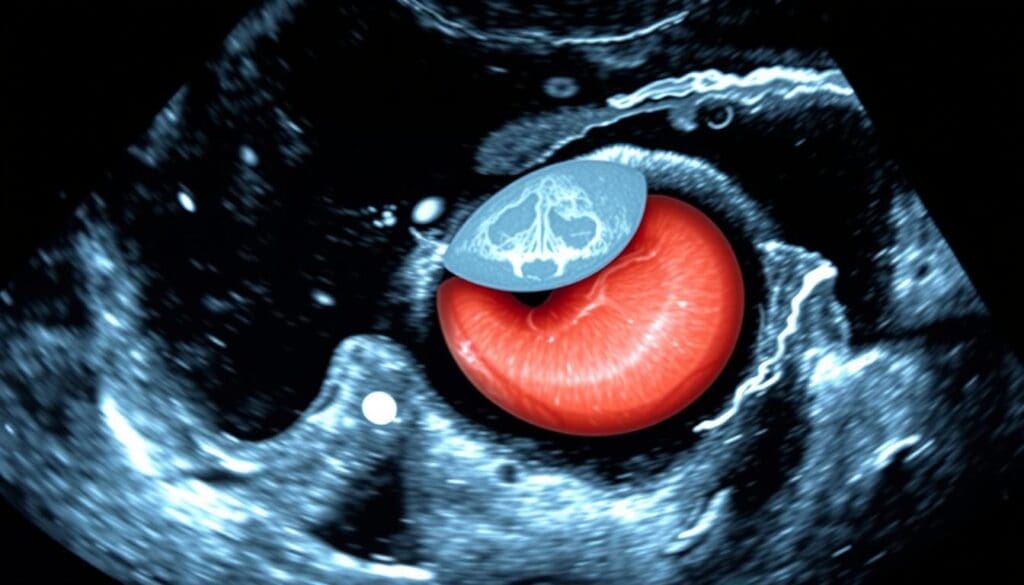

We use both transverse and longitudinal scans to see the aorta well. The transverse approach helps us check the aorta’s size and spot aneurysms. The longitudinal approach shows the aorta’s length and any issues like thrombi or wall problems.

Importance of Both Transverse and Longitudinal Documentation

It’s important to take images from both sides and lengths. Transverse images show the aorta’s size and any bulges. Longitudinal images tell us about the aorta’s length and any blockages or hardening.

| Transverse | Aortic diameter, aneurysms | Detection of irregularities |

| Longitudinal | Aortic length, thrombi, wall calcifications | Assessment of aortic morphology |